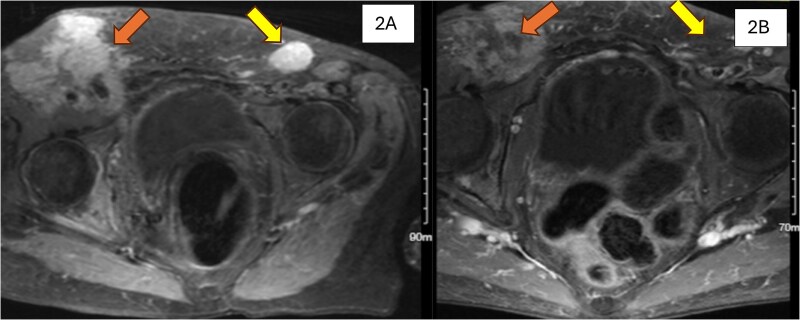

Late recurrence of ovarian cancer is exceedingly rare. We report a case of adenocarcinoma of Müllerian origin that developed 22 years after hysterectomy and bilateral salpingo-oophorectomy (BSO) for ovarian cancer in an 81-year-old woman with a pathogenic BRCA1 mutation. The patient underwent six cycles of reduced-dose carboplatin and paclitaxel, achieving remission with a dramatic decline in CA-125 levels. Women with BRCA mutations have a significantly increased risk of ovarian/tube/peritoneal cancer. Although risk-reducing BSO effectively decreases the risk of ovarian and fallopian tube cancers, the risk of peritoneal cancer remains substantial. This case not only illustrates the persistent lifetime risk of ovarian/tube/peritoneal cancer despite BSO but also underscores the need for reevaluation of prophylactic surgical strategies, particularly regarding the extent of peritoneal resection, in BRCA mutation carriers. Additionally, this case report demonstrated the efficacy of dose-modified chemotherapy for BRCA-associated cancers. Further research is warranted to refine surgical and therapeutic strategies for patients with BRCA mutation.